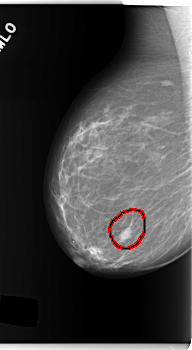

C_0140_1.RIGHT_MLO

FILE: C_0140_1.RIGHT_MLO.OVERLAY

TOTAL_ABNORMALITIES 1

ABNORMALITY 1

LESION_TYPE MASS SHAPE OVAL MARGINS MICROLOBULATED

ASSESSMENT 4

SUBTLETY 5

PATHOLOGY MALIGNANT

TOTAL_OUTLINES 1

BOUNDARY